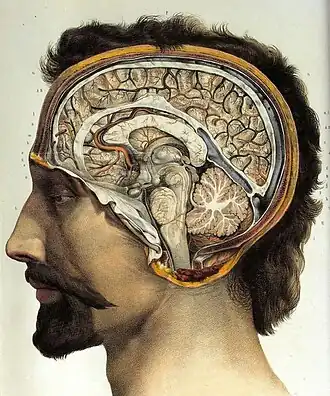

O cérebro, que consiste nos hemisférios cerebrais, forma a maior parte do encéfalo e recobre as outras estruturas cerebrais[6] A região externa dos hemisférios, o córtex cerebral, é a massa cinzenta, consistindo de camadas corticais de neurônios. Cada hemisfério é dividido em quatro lobos principais - o lobo frontal, o lobo parietal, o lobo temporal e o lobo occipital.[7] Três outros lobos são incluídos por algumas fontes, que são um lobo central, um lobo límbico e um lobo insular.[8] O lobo central compreende o giro pré-central e o giro pós-central e está incluído, pois forma um papel funcional distinto.[8][9]

O cérebro, o tronco cerebral, o cerebelo e a medula espinhal são cobertos por três membranas chamadas meninges. As membranas são a dura-máter resistente; a aracnóide e a pia-máter interna, mais delicada. Entre a aracnoide e a pia-máter estão o espaço e as cisternas subaracnoides, que contêm o líquido cefalorraquidiano.[10] A membrana mais externa do córtex cerebral é a membrana basal da pia-máter e é uma parte importante da barreira hematoencefálica.[11] O cérebro vivo é muito macio, tendo uma consistência de gel semelhante ao tofu.[12] As camadas corticais de neurônios constituem grande parte da matéria cinzenta cerebral, enquanto as regiões subcorticais mais profundas dos axônios mielinizados constituem a matéria branca.[6] A substância branca do cérebro representa cerca de metade do volume total do cérebro.[13]

O cérebro é a maior parte do encéfalo e é dividido em hemisférios direito e esquerdo quase simétricos por um sulco profundo, a fissura longitudinal.[14] A assimetria entre os lobos é observada como uma petália.[15] Os hemisférios são conectados por cinco comissuras que abrangem a fissura longitudinal, a maior delas é o corpo caloso.[6] Cada hemisfério é convencionalmente dividido em quatro lobos principais; o lobo frontal, o lobo parietal, o lobo temporal e o lobo occipital, nomeados de acordo com os ossos do crânio que os cobrem.[7] Cada lobo ou lóbulo está associado a uma ou duas funções especializadas, embora haja alguma sobreposição funcional entre elas.[16] A superfície do cérebro é dobrada em cristas (giros) e ranhuras (sulcos), muitos dos quais são nomeados geralmente de acordo com sua posição, como o giro frontal do lobo frontal ou o sulco central, que separa as regiões centrais dos hemisférios. Existem muitas pequenas variações nas dobras secundárias e terciárias.[17]

A parte externa do cérebro é o córtex cerebral, composto de matéria cinzenta organizada em camadas. Tem 2 a 4 milímetros de espessura e é profundamente dobrado para dar uma aparência complicada.[18] Abaixo do córtex está a matéria branca cerebral. A maior parte do córtex cerebral é o neocórtex, que possui seis camadas neuronais. O resto do córtex é de alocórtex, que tem três ou quatro camadas.[19]